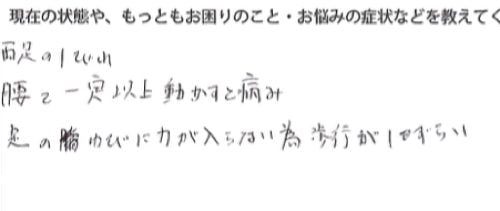

現在の状況を書いて頂くと

両足の痺れ

腰は一定以上に動かすと痛み

足の指に力が入らない為 歩行がしづらい

そんな状態です。